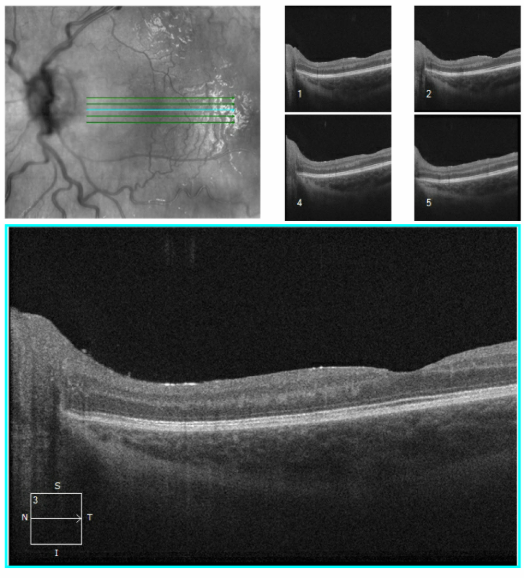

OCT from early Jan 2026, when she first re-presented with vision loss in the left eye and disc edema. Very poor quality with poor fixation, but you can get a better sense of the left optic disc edema from the macular images.

Better quality OCT from the end of Jan after the shunt placement. The macular rasters don't catch the disc this time, so it's hard to compare, but I'd say the edema has clearly improved.

There was an OCT done both pre- and post- shunt revision. The pre-op OCT has so much movement artifact, it is difficult to interpret, but you can still see the disc edema subjectively. The post-op OCT shows significant atrophy with an RNFL of around 76 I think. The cross sectional images show a reduction in the edema as well.